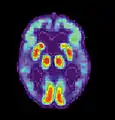

- Tomografia cu Emisiune de Pozitroni - PET

- Prin efectuarea unei Tomografii cu Emisiune de Pozitroni (PET), folosind molecule de glucoză marcate cu Fluor-18 (izotop radioactiv), se constată o reducere a utilizării glucozei (singurul element nutritiv al creierului), un așa zis "hipometabolism al glucozei", în special în regiunile frontale și parietale, în comparație cu persoanele normale.

Tomografie cu Emisiune de Positroni-PET . Imagini caracteristice la un pacient cu boala Alzheimer.